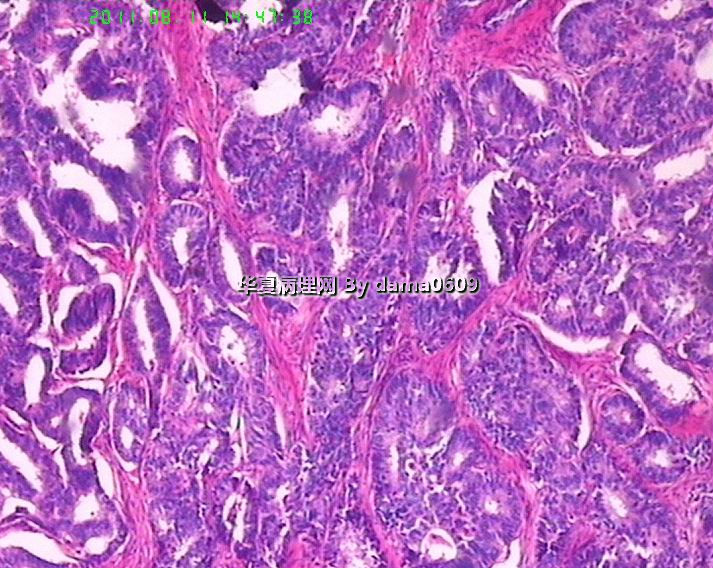

前列腺增生症标本内见有此病灶,请大家看看!!

• 前列腺增生症标本内见有此病灶,请大家看看!!图1

请老师们帮看看,够癌了吧------前列腺腺泡腺癌。核仁不十分明显!!

前列腺腺癌,个人认为还是有核仁的,应该不需要各个都有核仁吧?

前列腺腺癌,gleason3

间质已有浸润,癌无疑

前列腺癌,倾向导管型。

核仁也是仁呀,不能要求太高。我认为该病例核仁已经很明显了。

有一种前列腺腺癌--子宫内膜样腺癌,很象的

前列腺腺癌gleason3+3,伴HGPIN,